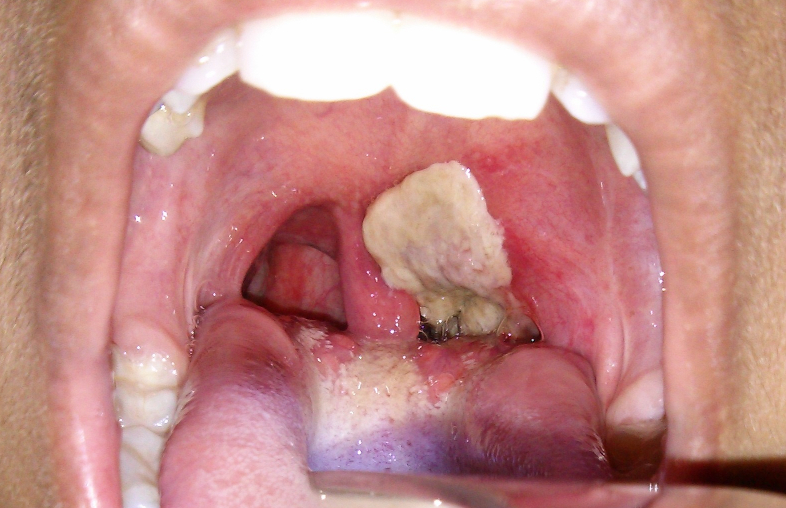

Điều gì làm cho bạch hầu trở nên nguy hiểm?

Theo Trung tâm Phòng ngừa và Kiểm soát Dịch bệnh Hoa Kỳ (CDC)cho biết, bạch hầu chỉ trở nên nguy hiểm và gây bệnh nghiêm trọng cho người khi vi khuẩn bạch hầu (corynebacterium diphtheriae) bị nhiễm thể thực khuẩn, truyền thêm độc lực chết người cho bạch hầu.

Nhiều vi khuẩn thực sự nguy hiểm khi có độc tố được mã hóa bởi bộ gen của thể thực khuẩn. Nếu không có độc tố mã hóa, các loài vi khuẩn này sẽ hiền lành hơn nhiều – chúng ít gây bệnh hơn, hoặc thậm chí là không gây bệnh. Một số vi khuẩn nguy hiểm được kể đến làdịch tả(vibrio cholerae),bạch hầu(corynebacterium diphtheriae), clostridium botulinum, clostridium difficile, và lỵ shigella. Tại sao thể thực khuẩn lại mã hóa những chất độc này đến nay vẫn còn là điều bí ẩn.